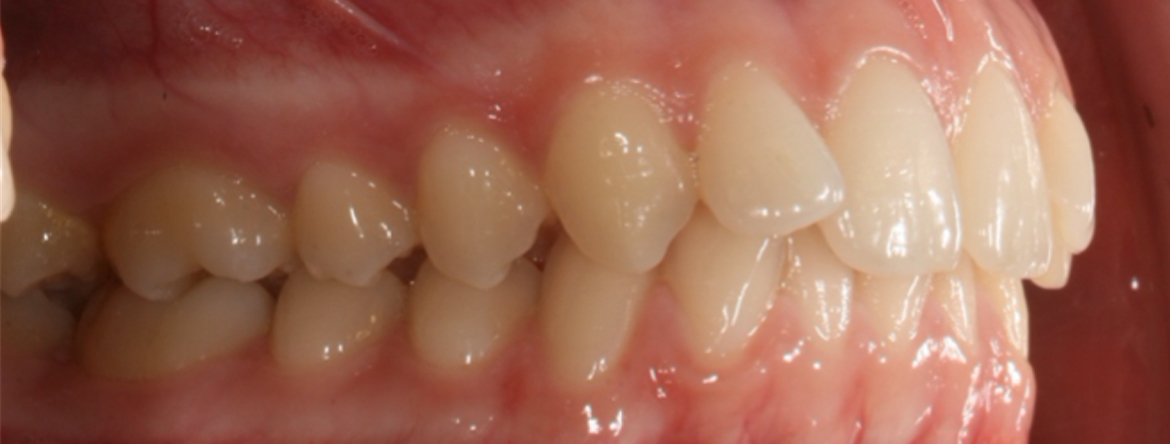

A má oclusão de Classe II é uma anomalia dentoalveolar, por vezes com comprometimento esquelético, que pode levar a alterações estéticas, fonéticas e funcionais.

O presente curso irá abordar a etiologia, diagnóstico e diferentes abordagens terapêuticas para correção desta má oclusão.